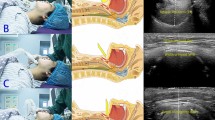

In the ultrasound group, a high-frequency hockey stick probe (L15-7io; Phillips, Andover, MA, USA) was placed along the midline of the neck and the transverse diameter of the subglottic area was measured using ultrasonography (Affiniti70; Phillips), with slight extension of the neck before intubation. Facemask ventilation was stopped to limit fluctuation during ultrasound acquisition. The subglottic transverse diameter was measured using the dimension of the air-mucosa interface within the bilateral inner margin of the cricoid cartilage, which appeared as a round hypoechoic structure (Fig. 1). The narrowest subglottic diameter revealed by the three ultrasound images was selected. Subsequently, the make of the tracheal tube, whose OD was smaller than the selected subglottic diameter, was deemed to be the appropriate size. The difference between the two values was less than 0.5 mm to allow free passage of the tube and adequate sealing. Intubation was performed with this size. The insertion depth was determined by auscultation and confirmed with lung ultrasonography. Lung ultrasonography was performed by placing the transducer on the third intercostal space along the midclavicular line on both sides of the chest for visualizing pleural sliding and lung expansion, which was synchronized with manual ventilation (Fig. 2). The tube tip was advanced gently into the right or left mainstem bronchus, until unilateral lung sound was lost, and pleural sliding and lung expansion was not visualized on one side of the lung on scanning. After confirming the endobronchial position of the tube tip, the tube was withdrawn slowly until bilateral lung sounds were auscultated and bilateral pleural sliding and lung expansion were visible, and then further withdrawn, so that the tube tip was positioned 2 cm above the carina The tube was secured to the lower lip and inflation of tube cuff was determined with the same methods as those used in the conventional group.

Ultrasonographic measurement of the transverse subglottic diameter of the cricoid cartilage. The cricoid cartilage appears as a round hypoechoic structure with hyperechoic edges, composed of perichondrium. The transverse subglottic diameter is determined by measuring the dimension of the air-mucosa interface (between two crosses) within the bilateral inner margin of the cricoid cartilage.